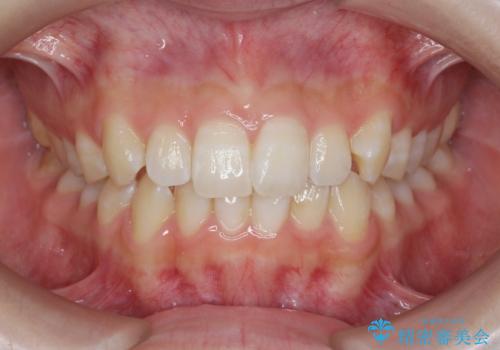

[マウスピース矯正] 海外留学中でも可能な矯正治療

担当医 大元洋佑